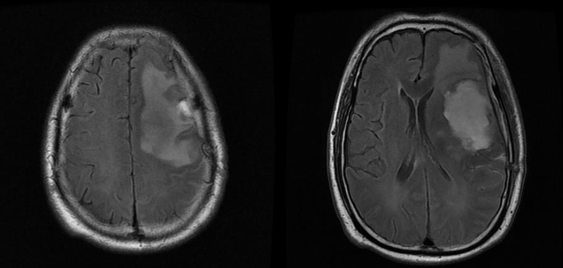

分享一例脑胶质母细胞瘤病例(原创)

右侧顶枕叶巨大胶质母细胞瘤